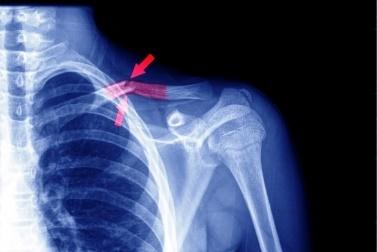

A csonttörések a test bármely csontját érinthetik, de leggyakrabban a végtagokon fordulnak elő. Gyakori a kulcscsont, a felkar, az alkar, a könyökcsúcs, az orsócsonti tányér, valamint a csukló és a kézközépcsontok törése, illetve az ujjakon is előfordulhat. Az alsó végtagon jellemző a lábszár, a sarokcsont, a lábközépcsont, az ujjpercek, a combcsont, a sípcsont, valamint a kül- és belboka törése, amelyek többnyire esés vagy nagyobb ütés következtében alakulnak ki.

Csonttörés – orvosi szakkifejezéssel a csontszövet folytonosságának megszakadása – számos ok miatt bekövetkezhet. Okozhatja valamilyen közvetlen erőhatás – esés, ütés vagy más baleset –, de különösen idős korban bekövetkezhet spontán módon, valamilyen betegség, például daganatos elváltozás, csontritkulás vagy vitaminhiányos állapot következményeként is. A csonttöréseknek két alaptípusa – a sérülés jellegétől függően – a nyílt és a zárt törés.

A csonttörés többnyire nem csak a csontszövet, de a csontot borító csonthártya, valamint a környező erek és idegek sérülésével, illetve az izmok bevérzésével, vérömlennyel és duzzanatával is jár. A csonttörés biztos jele a törött csontrészek megjelenése a bőrön keresztül – ezeket nyílt törésnek hívjuk. A fedett törések biztos jele, ha a sérült végtag alakja deformálódik, vagy ha hallható és érezhető a törött csontvégek ropogása. A koponyaalapi törés biztos jele az agyat és a gerincvelőt körülvevő folyadék csorgása a fülön vagy az orron keresztül. A csonttörést valószínűsíti az érintett testrész fájdalma, illetve működésének zavara vagy teljes kiesése.

A csonttöréses betegek vizsgálata során a traumatológus elsősorban a csonttörés biztos jeleit kutatja, majd megvizsgálja a lágyrész-sérüléseket, ellenőrzi a keringést és a végtag hőmérsékletét a törés környezetében, valamint megvizsgálja a mozgató- és az érzőidegek működését. A vizsgálatok nélkülözhetetlen eszköze a kétirányú röntgenfelvétel, amelynek során a törött testrészről két, egymásra merőleges irányú felvételt készítenek. Az esetleges CT-vizsgálat a csontok, az MRI-vizsgálat pedig a lágyrészek sérüléseinek pontosabb feltérképezésére ad lehetőséget. Ha a törés – különösen bordatörés – kapcsán felmerül a folyadék- vagy a léggyülem lehetősége, azt ultrahanggal lehet igazolni, komoly ér- illetve idegsérülés gyanújánál pedig kontrasztanyagos vizsgálat elvégzése lehet indokolt.